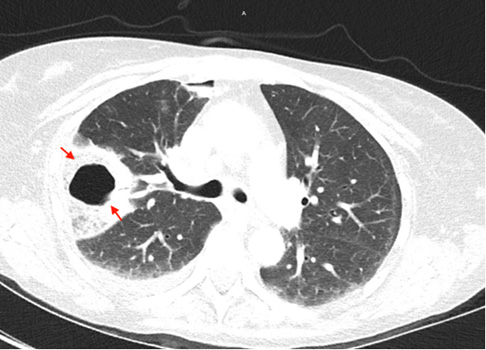

A 53year old woman with a history of alcohol use disorder, COPD, asthma and >20 pack year smoking history presented to the emergency department for two days of worsening shortness of breath and cough with rusty brown sputum and occasional streaks of blood. She denied any fever or chills but endorsed night sweats which she attributed to menopause. On initial evaluation the patient was afebrile, hemodynamically stable and saturating well on room air. Initial work up was positive only for an elevated c-reactive protein of 441. Chest x-ray showed a cavitary lesion in the right upper lobe of the lung measuring 5.7x4.3cm and bibasilar subsegmental atelectasis. Notably, the patient had a chest x-ray 6 months prior that showed no cavitary lesions. The patient was put on oxygen supplementation to assist in resolution of the atelectasis. Subsequent CT chest imaging on the same day showed a 5.1x4.3x5.7 cm thick-walled cavitating lesion in the right upper lobe with right bronchial lymphadenopathy and a small right apical pneumothorax and mild basilar effusion. The patient was put in isolation due to concerns for tuberculosis and further work up was sent including mycobacterial culture along with another infectious workup. Rheumatologic workup was also done secondary to concerns for granulamtosis with polyangitis. She was started on broad coverage with ceftriaxone, doxycycline, and metronidazole (Figures 1-3).

Figure 1: Single view chest X-ray showing thick walled cavitary leision in the right upper lobe 5.7x4.3cm; Yellow Arrows.

Figure 3: CT chest showing small pneumothorax on the anteromedial aspect of the right lung apex; Red arrow.